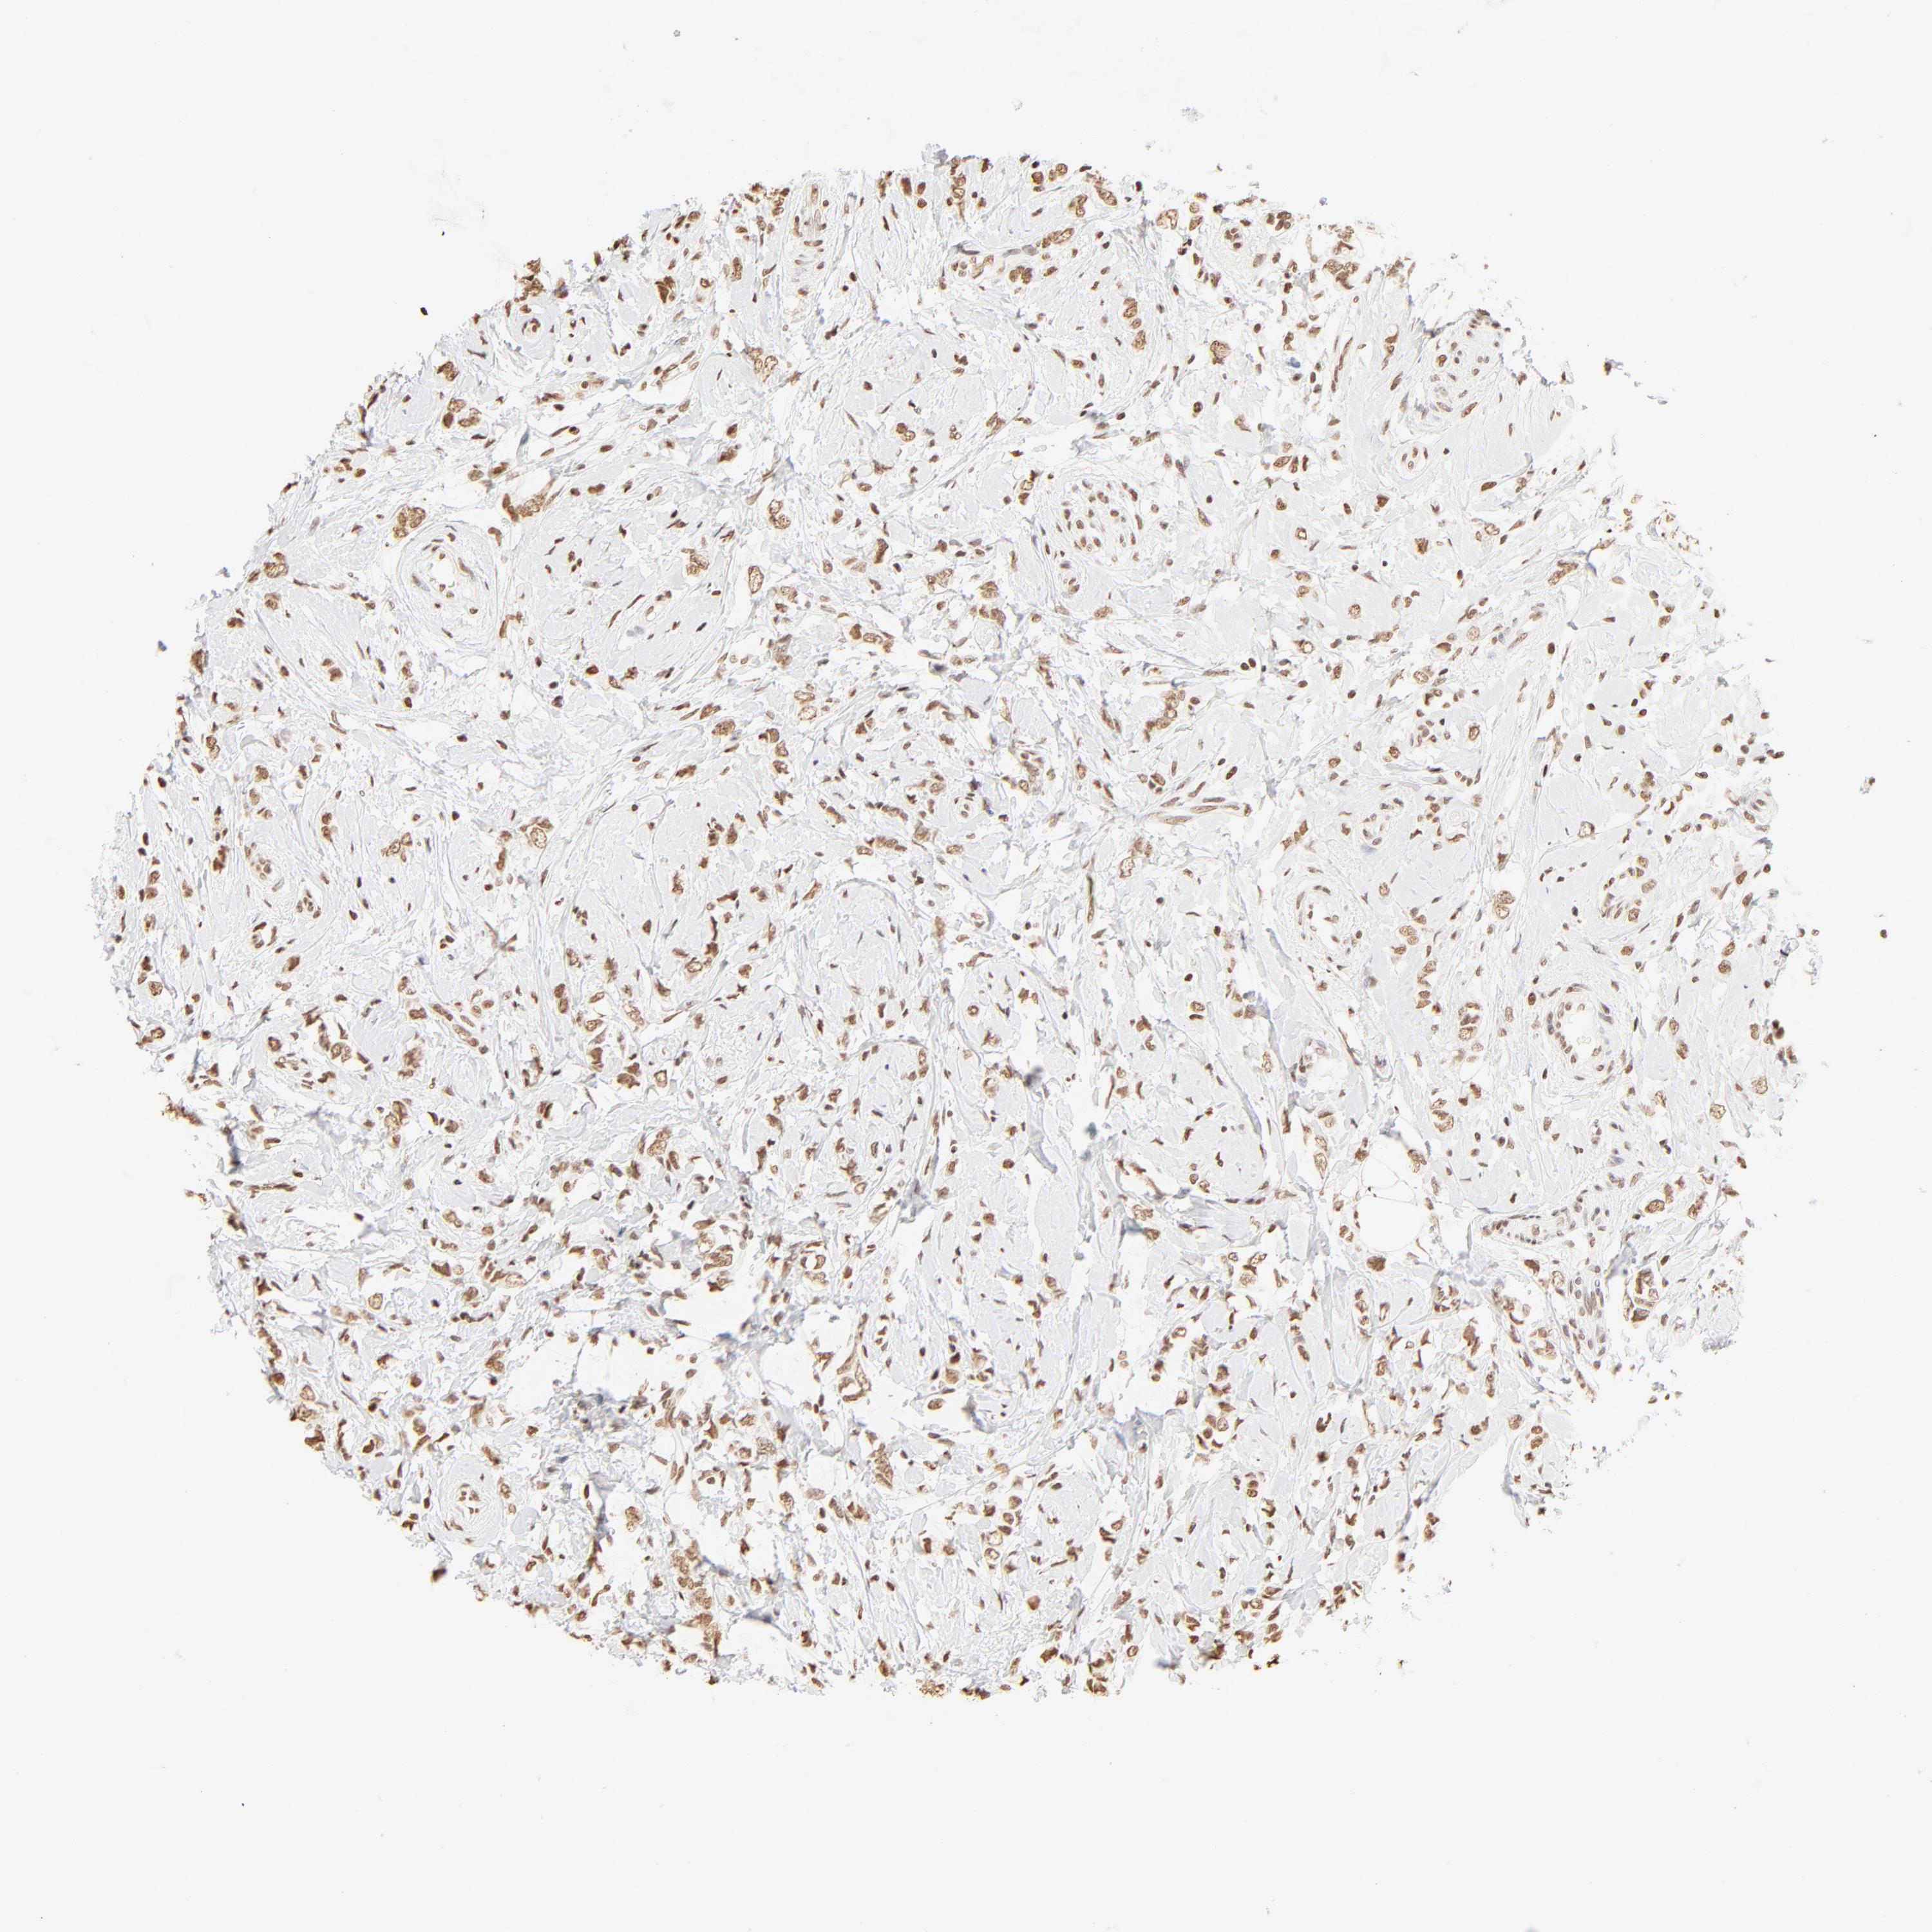

CANCER BREAST CANCER Show tissue menu

BRCA TCGA BRCA VALIDATION PROTEIN EXPRESSION